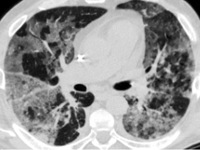

- КТ высокого разрешения. Помогает уточнить распространенность поражения легочной ткани, оценить стадию, активность и темпы прогрессирования фиброзного процесса.

КТ ОГК. Интерстициальная пневмония, участки «матового стекла» (красная стрелка) и ретикулярные изменения.

- Томографическое исследование дает более точные диагностические данные, чем рентгенография, оценивает строение легких и их способность к расправлению, выявляет признаки воспаления межуточной ткани, распространенность поражения, стадию, активность и темпы прогрессирования фиброзного процесса. На снимке видны очаги уплотнения ткани, снижение прозрачности паренхимы легких по типу матового стекла, сегментарные расширения бронхов – бронхоэктазы.